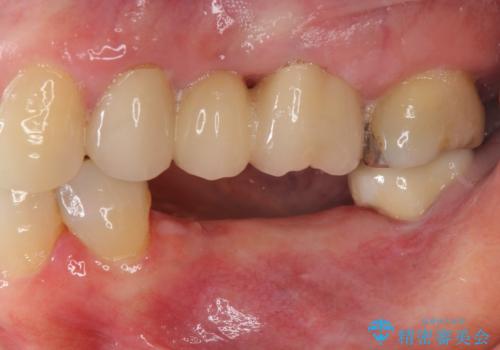

下顎骨隆起を用いた骨造成・インプラント補綴

- 歯を喪失してしまい、咬合機能の回復を求めて来院されました。

入れ歯ではなく、よりしっかりと噛めるようになるインプラント治療を希望されましたが、将来的な安定を見込むにはインプラント周囲の骨量が少ない状況でした。

舌側にある大きな骨隆起を除去するとともに、除去した骨と人工骨を用いてインプラント周囲の骨を造成します。